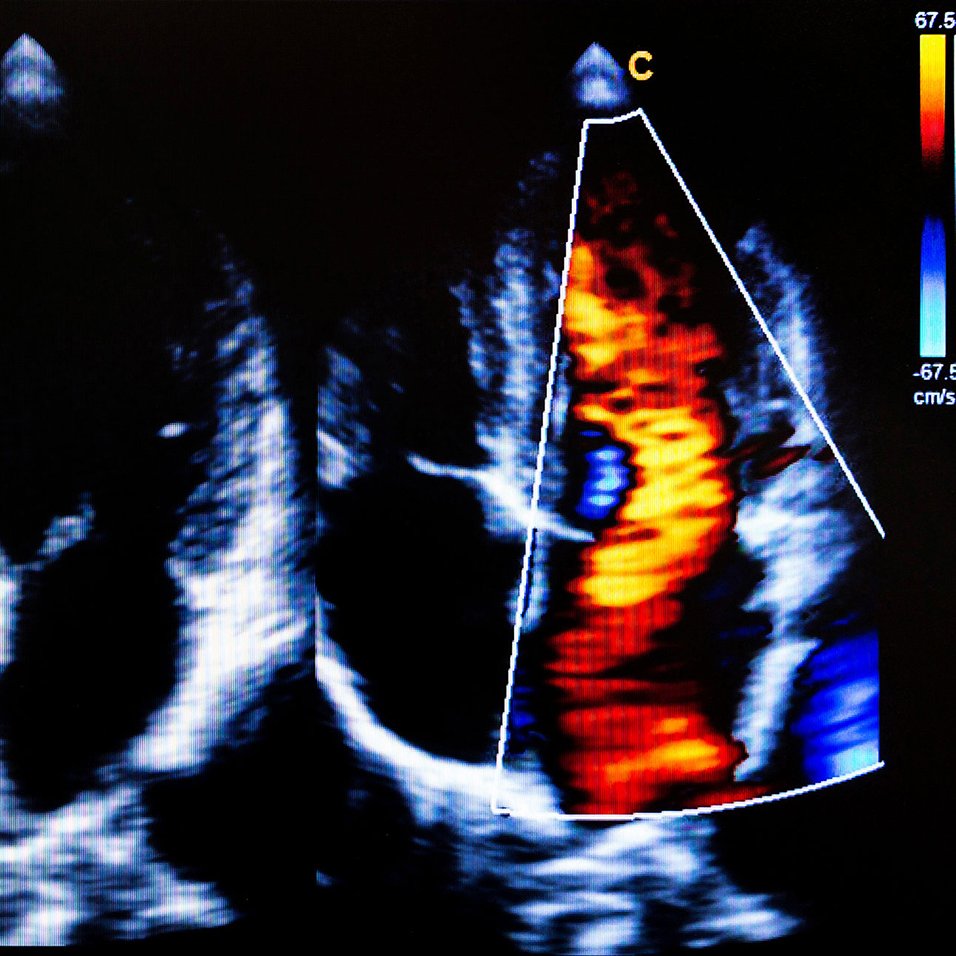

Comment retrouver des contractions cardiaques synchrones ?

Grâce à un pacemaker relié par des sondes au muscle cardiaque, il est possible de rendre au cœur une activité contractile synchronisée...

La congestion dans l’insuffisance cardiaque mieux traitée